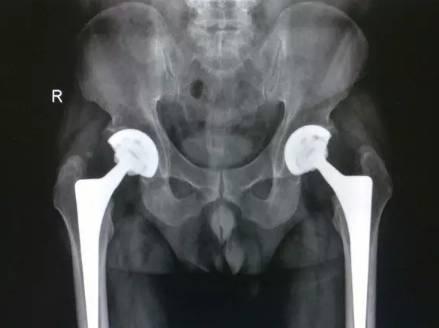

股骨头坏死,必须换关节吗?

治疗股骨头坏死的渊源